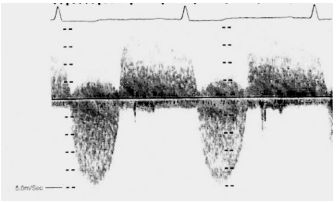

159.參考圖 A, B, C, 請問下列敘述何者錯誤?

(A) 此疾病早期 (early stage),還保有左心室收縮功能。 (B) 此疾病,左心室舒張末期壓力上升,影響左心房收縮血液至左心室,因此二尖瓣血 流 (mitral flow) 之 A 波通常變小。 (C) 此疾病,左心房壓力上升,影響肺靜脈血流 (pulmonary vein flow),造成肺靜脈血流 之流速在收縮期時 (S) 降低。 (D) 由於全面舒張期異常,因此,tissue Doppler 在二尖瓣環狀 (mitral annulus) 之 E’流 速通常小於 7 cm/sec。 (E) 此疾病主要是因為心包膜異常變厚,或是發炎,或是鈣化,而導致舒張期填充 (diastolic filling) 異常。